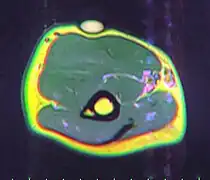

A physical exam is typically the easiest way to diagnose it. Rarely, a tissue biopsy or imaging may be required. The imaging modality of choice is magnetic resonance imaging (MRI), because it has superior sensitivity of distinguishing it from liposarcoma as well as mapping the surrounding anatomy.[20]

![T1 MRI of the same lipoma: High intensity signal mass with regions of ill-defined margins.[21]](./_assets_/0c70a452f799bfe840676ee341124611/T1_MRI_of_thenar_intramuscular_lipoma.jpg)